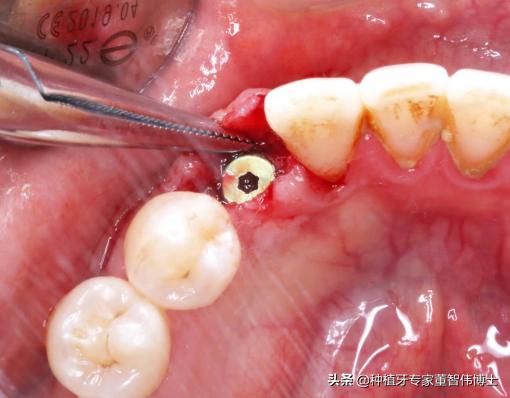

2期手术